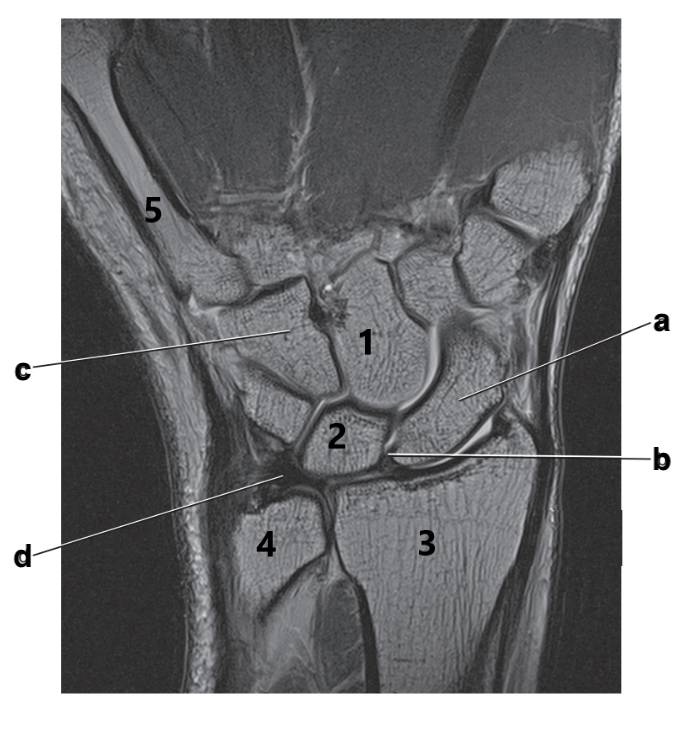

Hook of the hamate

What is the major stabilizing mechanism for the distal radioulnar joint?

Triangular fibrocartilage complex

What is # 4?

Ulna

Scaphoid

What ligamentous structure spans the wrist to create an enclosure for the passage of tendons?

Flexor retinaculum